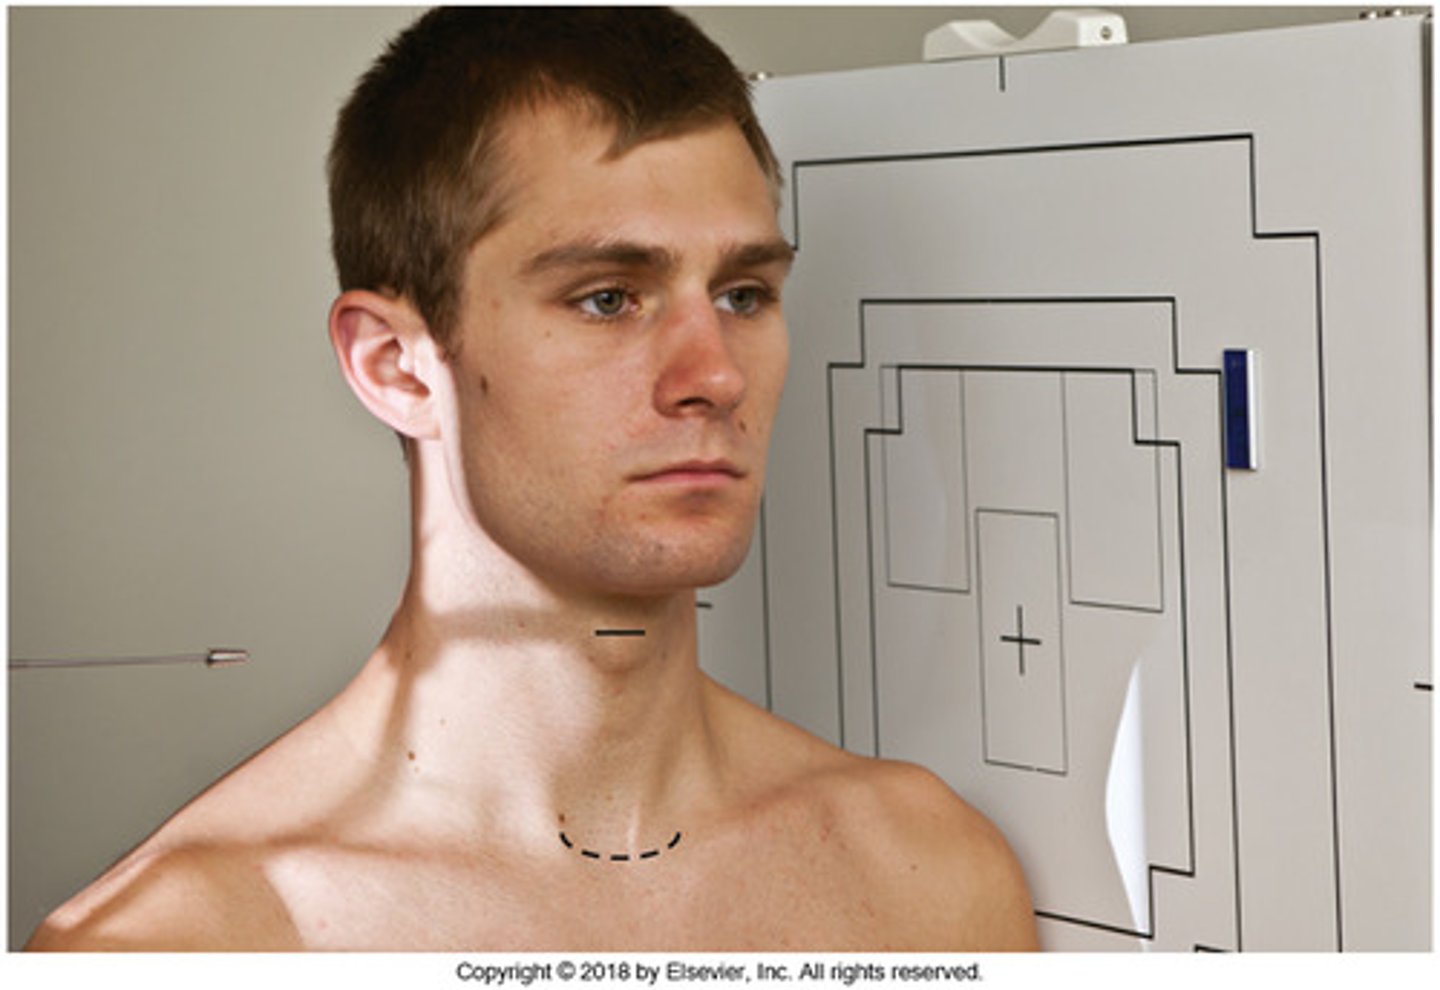

Go through the STAMPSBC list for the AP Axial C-spine

S - shielding around waist

T - 18 mAs @ 75 kVp

A - 15 degree cephalad

M - marker along curve of neck

P - back against board, chin elevated slightly

S - 40

B - suspend breathing

C - 10 x 12 lengthwise, can collimate to 8 x 10

Where do you center for the AP Axial C-spine?

C4 - C5